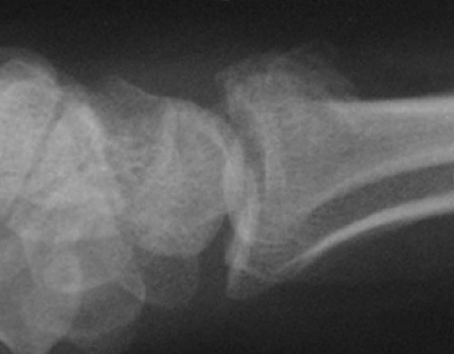

Radiocarpal fracture-dislocations are complex injuries characterized by dislocation of the radiocarpal joint (► Fig. 44.1). It is important to differentiate these from a Barton or reverse Barton (dorsal) fracture (► Fig. 44.2). Barton’s fracture involves a shear fracture of the articular surface of distal radius, with the fractured fragment attached to the carpus. In addition, the displaced fragment forms a substantial part of the distal radius articular surface. In contrast, radiocarpal fracture-dislocation is a high-energy injury with disruption of the radiocarpal ligaments. It is typically associated with a small cortical rim and/or radial styloid fracture (► Fig. 44.1).